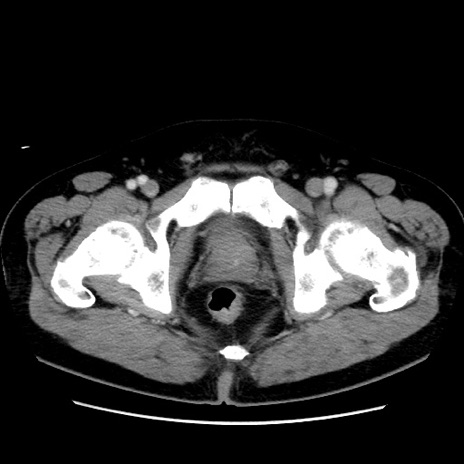

症例16(横断像)

【症例】 70歳代男性

【主訴】 腹痛、嘔吐

【現病歴】 約1ヶ月前より間欠的に腹痛と嘔吐あり、当院消化器内科を受診したところCTで多発する肝臓のLDAを指摘され、精査中であった。以降は消化器症状は安定していたが、2日前より嘔気と腹痛があり、同日より排便・排ガスが消失した。改善認めず、 本日、救急外来を受診した。

【既往歴】 大腸ポリープ切除後。

【身体所見】意識清明・会話良好、BT 36.3℃、BP 127/80mmHg、 P 80bpm、腹部:膨満あり、平坦・軟、上腹部正中および下腹部正中に圧痛あり、反跳痛なし、筋性防御なし。

【データ】WBC 7200、CRP 0.77